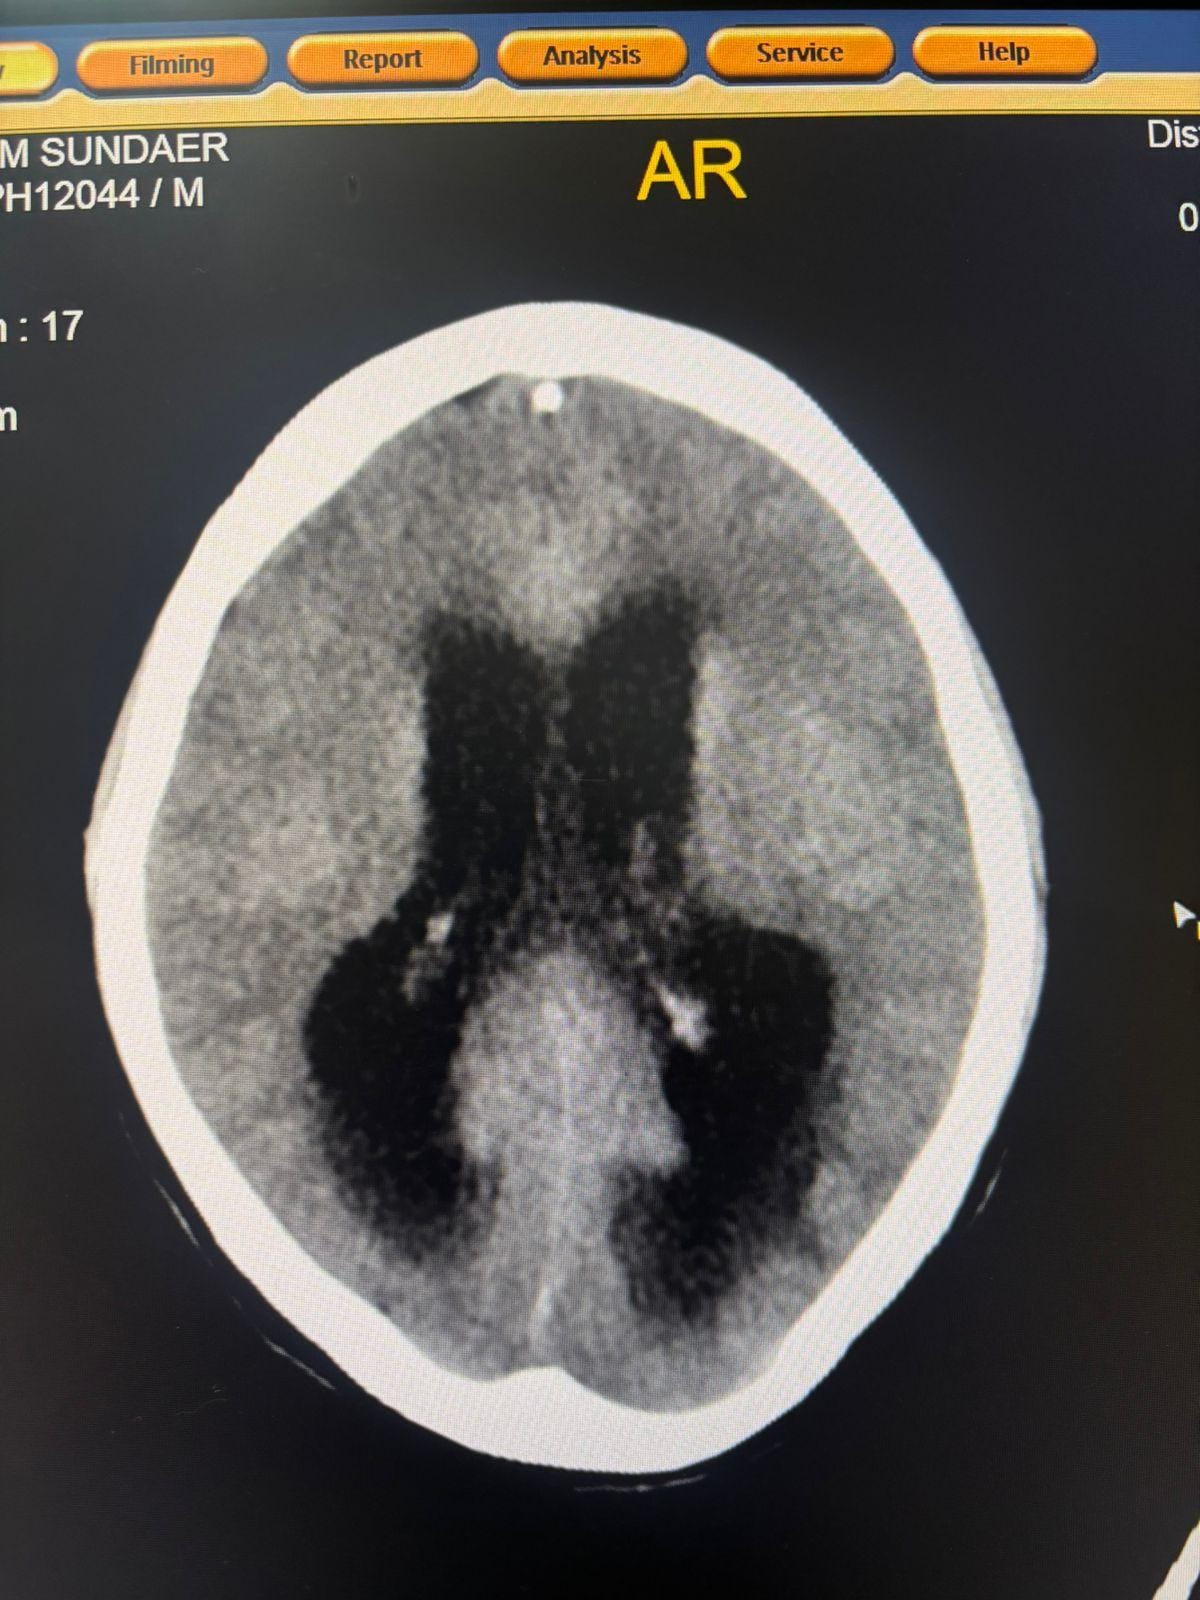

चिकित्सकों के अनुसार स्टेज–4 ट्यूबरकुलस मेनिन्जाइटिस में मृत्यु दर अत्यंत अधिक होती है। दवा अधूरी छोड़ने के कारण मरीज में हाइड्रोसेफेलस विकसित हो गया, जिससे मस्तिष्क में सूजन आ गई और वह पूरी तरह अचेत हो गया। इस अवस्था से मरीज का सुरक्षित बाहर आना जिले के लिए बड़ी चिकित्सकीय उपलब्धि माना जा रहा है।

मरीज के कोमा में होने और पीयूजे ऑब्स्ट्रक्शन के कारण किडनी फेल होने की स्थिति को देखते हुए आईसीयू में ही बेडसाइड पर परक्यूटेनियस नेफ्रोस्टॉमी (पीसीएन) की गई। यह जिले में पहली बार किया गया जीवनरक्षक हस्तक्षेप रहा। किडनी में ड्रेनेज ट्यूब डालने के बाद गुर्दों की कार्यक्षमता सुधरी, जिससे मस्तिष्क की सूजन का उपचार संभव हो सका। इसके बाद मरीज को होश आया और वह परिजनों से बातचीत करने लगा।